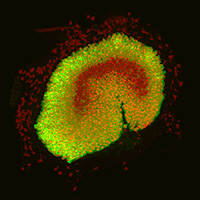

Hair cells (red) and associated supporting cells (green) in the sensory patch of a mouse utricle, part of the balancing apparatus of the inner ear. Credit: Joseph Burns, Ph.D., NIDCD.

Specialized sensory epithelial cells in the inner ear include hair cells and supporting cells, which provide the hair cells with crucial structural and functional support. Hair cells and supporting cells located in the cochlea—the snail-shaped structure in the inner ear—work together to detect sound, thus enabling us to hear. In contrast, hair cells and supporting cells in the utricle, a fluid-filled pouch near the cochlea, play a critical role in helping us maintain our balance. These cells detect how we move our heads and how our heads are positioned; this information tells our brain, for example, whether we are standing or lying down. The utricle is one of several structures and organs in the body that provide our sense of balance; together, they comprise the vestibular system.